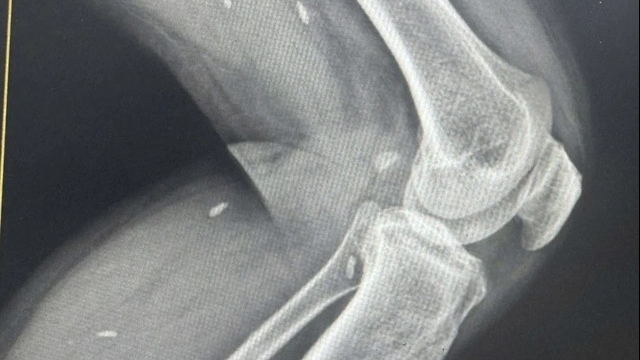

Trước đó vào ngày 13/6, tại Bệnh viện Chợ Rẫy cũng từng xảy ra vụ lùm xùm khi bệnh nhân Nguyễn Đức Th. bị gãy đốt sống ngực số 8 trong một lần trèo lên cao để lắp camera cho khách hàng. Tuy nhiên khi được chuyển lên BV Chợ Rẫy TPHCM, nam bệnh nhân lại bị khoan nhầm vào cẳng chân.